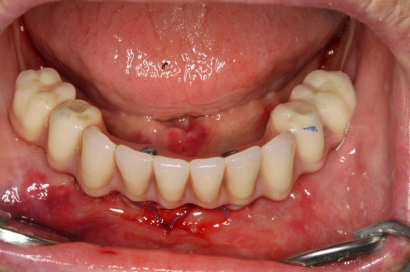

Během let může postupnou ztrátou zubů zůstat v ústech omezený počet zubů, které umožňují držení zubních náhrad.

V důsledku přetížení zbylých zubů např. houpavými pohyb snímacích náhrad dochází k uvolnění těchto zubů a držení můstků a protéz je tak velmi těžké. V těchto případech můžeme pomocí implantátů zvýšit počet pilířů a tím zabránit přetěžování a ztrátě zbylých zubů

Bezzubá čelist je hlavní indikací pro ošetření pomocí implantátů. Zejména celkové zubní náhrady v dolní čelisti mají velice nízkou stabilitu a držení díky velkému úbytku kosti.

S pomocí zubních implantátů můžeme díky různým kotevním systémům (třmeny, kulové hlavy, Locatory) zajistit stabilitu a držení protézy nebo při použití většího počtu implantátů zhotovit pevné náhrady – můstky nalepené nebo našroubované na pevno na implantáty.

S těmito typy náhrad můžeme dosáhnout perfektní funkci, výbornou estetiku, fonetiku a současně zajistit u pacienta možnost dobré hygienickou péče a čištění, která je pro životnost implantátů velice důležitá.